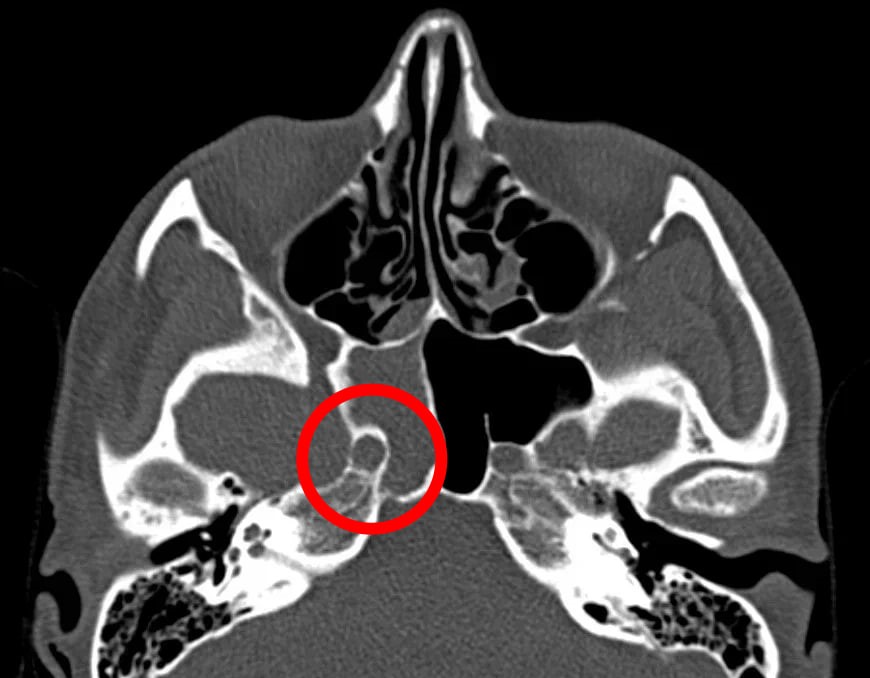

Жительница Нижнего Новгорода, долгое время связывавшая свои мучительные головные боли с магнитными бурями, обратилась к врачам и оказалась на операционном столе. Настоящей причиной недомогания оказался грибок, разросшийся в основной пазухе носа. На видеоэндоскопических снимках, сделанных во время операции, отчетливо виден тёмно-коричневый грибок, глубоко расположенный в пазухе.

Диагноз был поставлен после компьютерной томографии, которая выявила патологические изменения в области околоносовых пазух. По словам ЛОР-хирурга Григория Белозерова, операция проходила в зоне повышенного риска — буквально в миллиметре от внутренней сонной артерии, питающей головной мозг. Малейшая ошибка могла привести к необратимым последствиям.